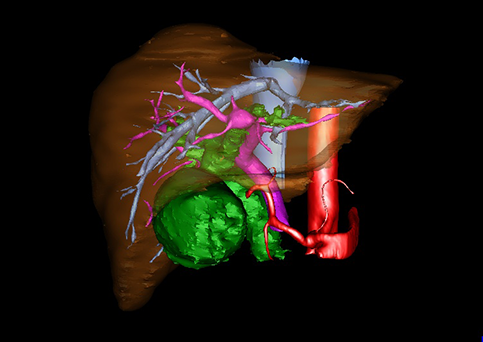

图12:先天性胆管扩张症梭状型合并左右肝管分别汇入胆总管囊肿三维重建虚拟肝脏、胆道显像

a 图为术前二维CT图像;b 图为CT经多平面重组技术(MPR)所得的三维重建图像,可粗略地判断病变胆管的位置;c 图为MRCP显示胆总管梭状扩张;d 图为术前Hisense CAS三维重建显示胆管的分布走形及其与肝内三套血管系统的解剖关系;e 图为胆道系统立体形态及与肝脏整体的空间关系,箭头处显示对于左右肝管分别汇入胆总管囊肿中,整个肝总管也明显扩张而成为囊肿的一部分。术前规划为先将囊肿完全切除,左右肝管合并成形后再与空肠吻合。